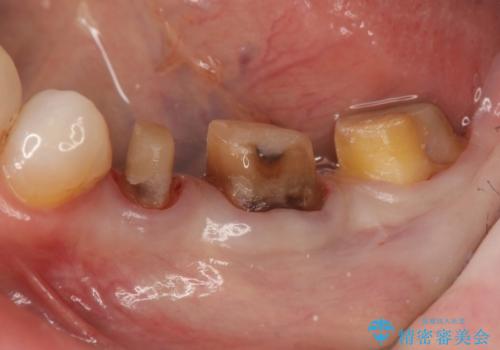

クラウン治療を行う場合歯ぐきの腫れが、クラウン製作の精密さにおいて問題点となることがあります。

このような場合、歯周外科を行うことでクラウン周囲の歯茎の状態を整備し精度に優れる治療を行うことができます。